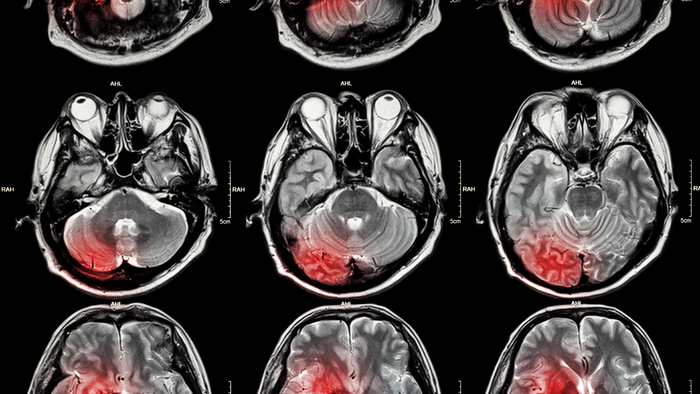

A new study has revealed that exposure to pollutants from petroleum refineries has a strong link to stroke rates across the Southern United States. The results were published today in IOP Publishing’s journal Environmental Research Letters.